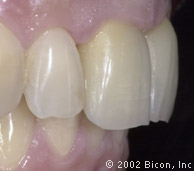

Окончательный результат. Превосходная эстетика!